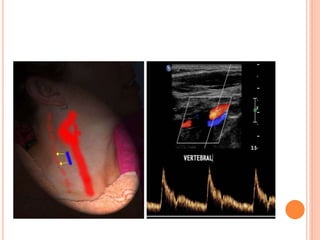

3- SUBCLAVIAN STEAL PHENOMENON

 refers to steno-occlusive disease of the proximal

subclavian artery with retrograde flow in ipsilateral

vertebral artery

VERTEBRAL TO SUBCLAVIAN STEAL

Presteal

Incomplete steal

Complete steal

Compared to bunny in profile